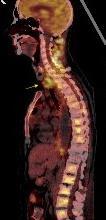

Densidad similar al músculo con estriaciones internas de grasa

Hallazgo incidental . Región infraescapular 2% de TC del tórax. Bilateral 60%.

Burt AM et al. Imaging review of lipomatous musculoskeletal lesions. SICOT J2017/ Murphey MD et al. From the archives of the AFIP: benign musculoskeletal lipomatous lesions. Radiographics. 2004